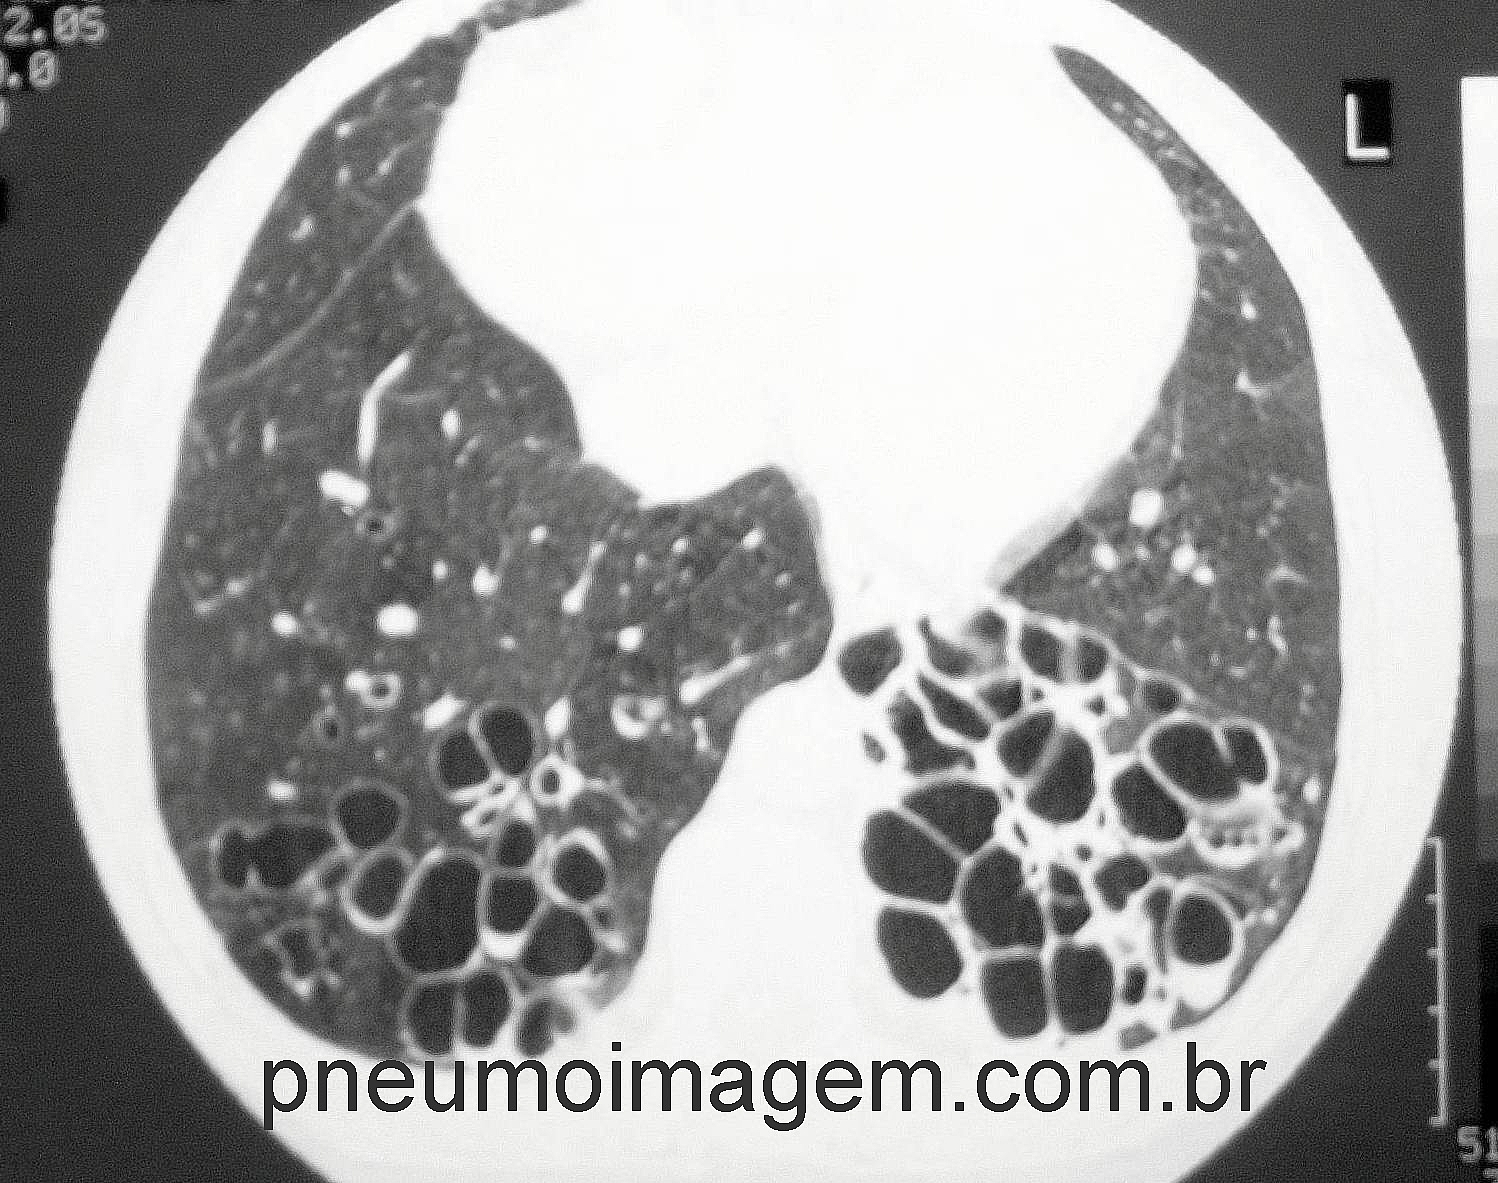

Veja imagens de bronquiectasias no PneumoImagem, clique aqui.